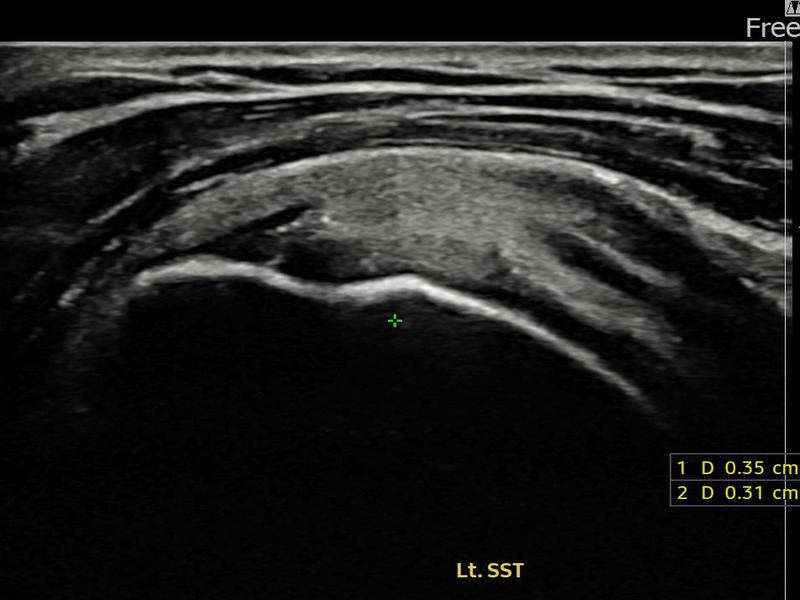

정ㅇㅇ님 · 좌측 극상근건 부분파열

좌측 어깨 통증이 오래 지속되어 내원하셨습니다. 초음파 검사에서 극상근건 부분파열이 확인되었으며, 어깨인대 축소봉합술 시행 후 장기 추적 초음파에서 힘줄 연속성이 완전히 회복된 것이 확인되었습니다.